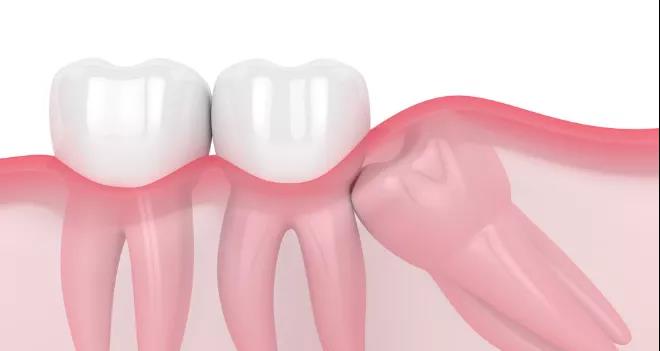

4、侵犯邻牙

如果智齿的萌生空间不足,与邻牙无法形成良好的邻接关系,就容易造成塞牙,导致邻牙龋坏或者牙槽骨吸收。

并且智齿生长的角度往往是歪七扭八的,可能会顶着相邻牙齿的齿面,让被挤压的牙齿有被蛀的风险。

智齿阻生的部分情况

最让人头疼的是横着长的智齿,没有萌出反而顶着邻牙的牙根,导致牙根之间的牙槽骨被吸收。

而且牙槽骨吸收所造成的的伤害是是无法挽回的,最终发展下去,会两败俱伤。

不仅智齿需要拔除,邻牙可能得一块儿被拔掉,十分影响咀嚼功能。